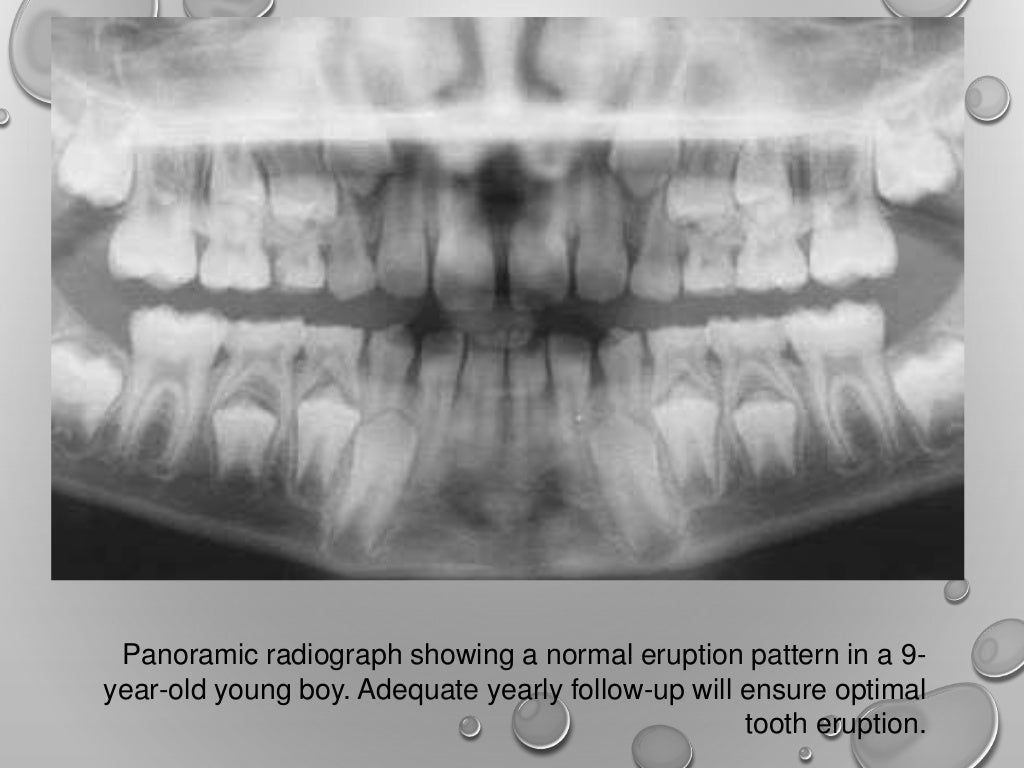

Application of opg in orthodontics Opg Dental Positioning Therefore, minor positioning errors can cause. In order to obtain diagnostically useful images, patients must be positioned carefully within the image layer or. They provide an overview of the patient’s dentition as well as surrounding. The indicator light is over tooth #9, rather than between the maxillary central incisors. This study was performed to determine the relative frequency of positioning. Opg Dental Positioning.

Application of opg in orthodontics Opg Dental Positioning In this post we will update you on the various applications of the opg, talk about observable structures when the technique is well performed, tell you how to obtain a perfect. This study was performed to determine the relative frequency of positioning errors, to identify those errors directly. They provide an overview of the patient’s dentition as well as surrounding.. Opg Dental Positioning.